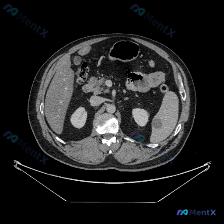

整理了一份非常有意思的影像读片资料,虽然只有单层CT平扫,但信息量其实很大,值得拿出来梳理一下思路。 --- 【影像所见】 这是一张腹部CT横断面软组织窗图像: 1. 脾脏(核心异常):脾实质内可见明显的低密度病变,形态呈类圆形,范围较大,占据了脾脏较大比例的实质区域。病灶密度不均匀,边缘尚可见残留...

整理了一份最近看到的腹部CT病例资料,重点在于脾脏的异常表现,结合分析报告说说思路。 先看影像基础情况 这是一份横断面腹部增强CT(软组织窗)的描述: - 脾脏:实质内可见片状低密度区,边界相对模糊,位置在脾门附近及脾实质中部; - 肝脏、胃、血管等:其余腹部实质脏器、腹腔脂肪间隙、脊柱肌肉等未见明...

整理了一个近期看到的病例资料和分析思路,分享给大家。 --- 【基本影像信息 - 检查方法: 上腹部CT横断面(软组织窗) - 影像核心表现: - 图像质量良好,解剖结构显示清晰; - 肝脏形态大致正常,肝实质密度尚均匀; - 脾脏:形态饱满,实质内可见较大的类圆形低密度灶,边界尚可辨认,中心密度低...

今天整理了一个很有代表性的腹部CT偶然发现病灶的病例,主要是想和大家分享一下这类「脾内孤立低密度灶」的分析思路。 先看影像与基本情况 这是一份上腹部CT横断面软组织窗图像的客观描述: - 肝脏:形态、密度大致正常,无明显大占位,无腹水。 - 脾脏:大小形态基本正常,脾实质内可见一个类圆形局灶性低密度...

今天整理了一个很有代表性的腹部CT读片病例,关于脾脏孤立低密度灶的鉴别,感觉很容易一开始就往「肿瘤」上想,但其实良性的可能性非常大,把完整的思路跟大家分享一下。 --- 先看影像和基本情况 这是一张腹部CT横断面软组织窗的平扫图像: - 肝脏、胰腺、双肾:基本正常,未见明确占位或结石,胰周脂肪间隙清...

整理了一份关于“脾脏下极局灶性低密度影”的读片思路,感觉这里特别容易踩坑,分享出来和大家一起讨论。 先看影像核心事实 这份是上腹部CT平扫(软组织窗)的单张横断面图像: - 肝脏:轮廓、密度基本正常,未见明确占位 - 脾脏:大小形态正常,但下极靠近背侧边缘处可见一处局灶性低密度影,边界相对清晰,密度...